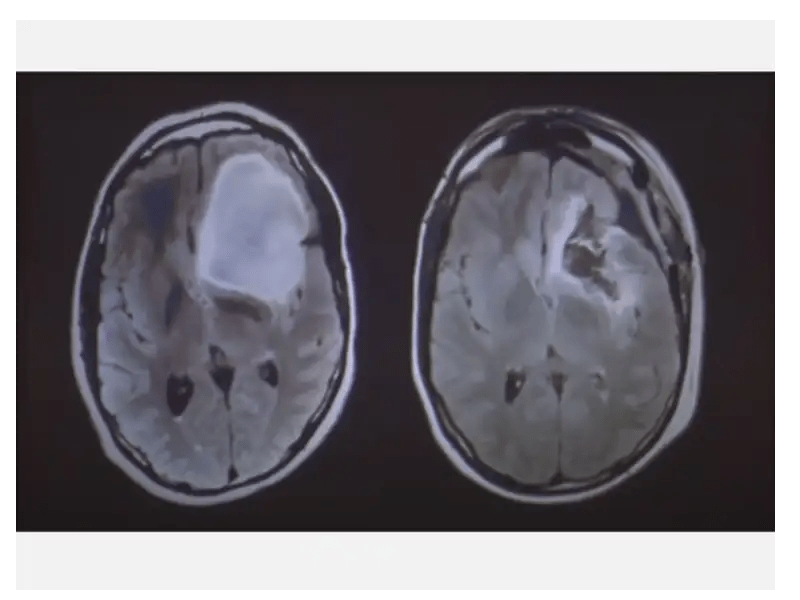

World Brain Tumour Day Never Ignore Warning Signs Netmeds

World Brain Tumour Day Never Ignore Warning Signs Netmeds from www.netmeds.com